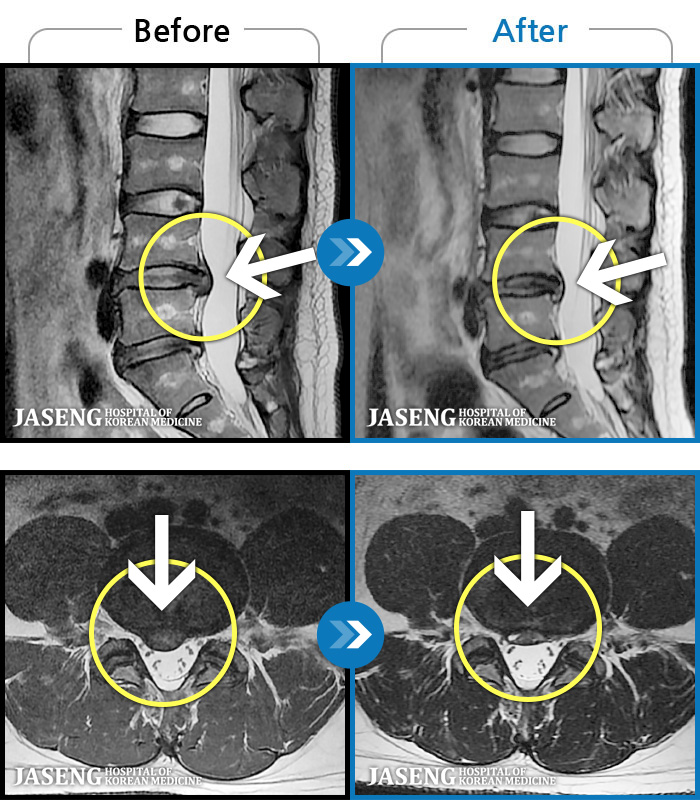

63 MRI ũ ʸ Ȯϼ.

MRI ġ

Ƹ ϰ ־.

õ

ȯ

㸮ũ

¥

2025.08.01

ȸ

8,449

[õ] 25.03.18~25.07.22

ȯںп Ǹ ǿ ԿǾ, ο ġ ۿ Ƿ ġḦ Ͻñ ٶϴ.